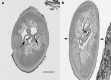

A 22-month-old girl presented with neck pain and stiffness and magnetic resonance imaging showed an extradural mass extending from C2 through the C4 level with moderate to severe compression of the cord. A left unilateral C2-C4 laminectomy was performed revealing an extradural rubbery tumor; a small biopsy was obtained. Examination of stained tissue revealed the presence of a parasitic worm that was identified as a gravid female Onchocerca lupi. A magnetic resonance imaging at 7 weeks follow-up showed a significantly decreased size of the enhancing lesion and the patient's symptoms gradually resolved. This is the first report of zoonotic O. lupi in the United States. The parasite has been reported in dogs and cats in the western United States, and from people in four cases reported from Europe. A great deal more needs to be learned, including full host range and geographic distribution, before we fully understand O. lupi infections in animals and man.